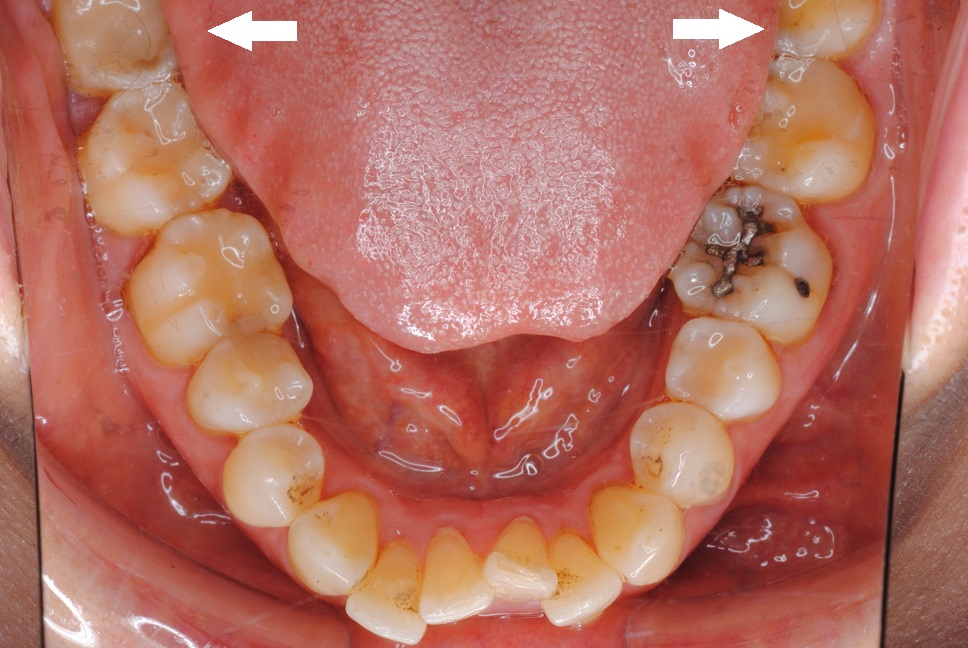

場合によっては、親知らずが正しい位置に移動するための十分なスペースが口内にない場合があります。歯肉を斜めに突き破ったり、部分的にしか突き抜けなかったりすることがあります。これが発生すると、 埋伏親知らずと呼ばれ、痛みや感染症などの問題を引き起こす可能性があります。

歯が歯茎の途中までしか生えていない場合、食べ物が歯と歯茎の間に挟まりやすくなります。また、これらの歯を清潔に保つことが難しくなり、感染症や虫歯につながる可能性があります。

ただし、親知らずが歯茎を完全に突き抜けて生えている場合でも、問題が発生する可能性があります。斜めに生えていると、口の中や歯茎をこすってしまう可能性があります。他の歯を押して痛みを引き起こす場合があります。

口の中に歯を入れる十分なスペースがない場合、親知らずの抜歯手術が必要になる場合があります。歯が影響を受け、感染が促進される可能性があります。斜めに生えた親知らずは痛みを感じることがあります。